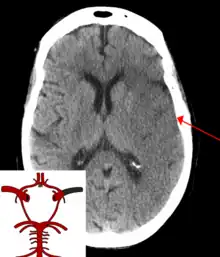

Intracerebral hemorrhage

It generally occurs in small arteries or arterioles and is commonly due to hypertension,[58] intracranial vascular malformations (including cavernous angiomas or arteriovenous malformations), cerebral amyloid angiopathy, or infarcts into which secondary hemorrhage has occurred.[2] Other potential causes are trauma, bleeding disorders, amyloid angiopathy, illicit drug use (e.g., amphetamines or cocaine). The hematoma enlarges until pressure from surrounding tissue limits its growth, or until it decompresses by emptying into the ventricular system, CSF or the pial surface. A third of intracerebral bleed is into the brain's ventricles. ICH has a mortality rate of 44 percent after 30 days, higher than ischemic stroke or subarachnoid hemorrhage (which technically may also be classified as a type of stroke[2]).